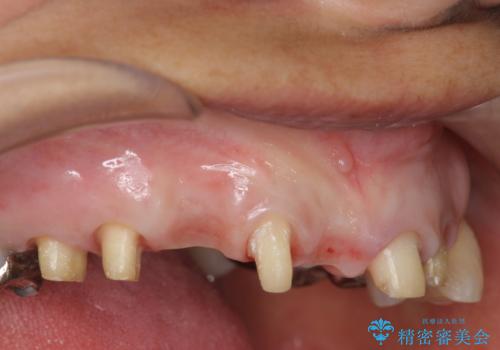

- 前歯を噛みしめにより失い、さらに犬歯もグラグラになり全く噛めなくなり改善を求めて来院されました。

過度な力がかかり周囲の骨に高度な吸収が見られた犬歯は抜歯し、機能・審美性の回復をより咬合力に対して抵抗力のあるブリッジ補綴にて対応します。

- 56円(仮歯・フルジルコニアクラウン×7)費用は治療当時の料金となります